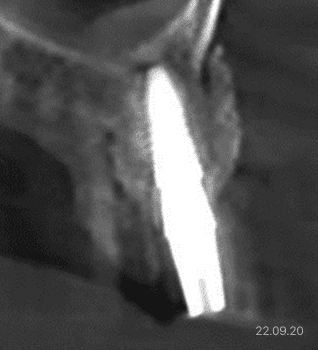

하치조신경과의 거리가 2~3mm에 불과한 부위처럼,

뼈의 높이를 증가시켜야 하는 고난도 뼈이식은 매우 정밀하고

복잡한 수술로 높은 기술력과 비용이 요구됩니다.

하치조신경과의 거리가 2~3mm에 불과한 부위처럼,뼈의 높이를 증가시켜야 하는 고난도 뼈이식은 매우 정밀하고 복잡한 수술로 높은 기술력과 비용이 요구됩니다.반면, 잇몸뼈의 구조가 비교적 온전한 부위에 가볍게 진행하는 단순 뼈이식은 난이도와 비용 모두 낮은 편입니다. 따라서, 각 부위별 해부학적 구조와 개인의 상태에 따라 맞춤형 진단과 계획이 선행되어야 합니다.

하치조신경이 중요한 이유

하치조신경은 아래턱 치아와 입술, 턱 부위의 감각을 담당하는 신경으로, 하악골 내부의 하치조관을 따라 주행합니다. 이 신경은 임플란트 식립, 발치, 또는 턱뼈 관련 수술에서 반드시 고려해야 할 중요한 해부학적 구조로, 손상될 경우 하순과 하악 치아에 감각 이상이나 저림, 통증 등의 증상이 발생할 수 있습니다. 따라서 정확한 CT 진단을 통해 하치조신경의 위치와 주행 경로를 사전에 파악하고, 임플란트를 식립할 때는 신경과 최소 2~3mm 이상의 안전 거리를 확보하는 것이 매우 중요합니다.